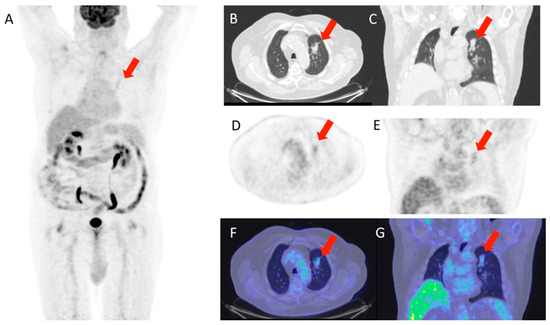

Figure 1 and Figure 2 show, respectively, examples of patients with lung relapse and a patient with phlogistic reaction to EBRT. In detail, Figure 1 shows images of a patient (male, 68 years old) with lung recurrence; PET/CT images with 18F-FDG are shown of a patient diagnosed with right lung adenocarcinoma who underwent surgery two years earlier and subsequently underwent radiotherapy for right lung recurrence, and the contrast-enhanced CT scan (Figure 1B) performed three months after the end of radiotherapy showed extensive pulmonary thickening in the right lung. Figure 2 shows an example of a patient with pulmonary inflammation: it shows the 18F-FDG PET/CT scan of an 82-year-old male patient diagnosed with left lung adenocarcinoma who underwent RT. The chest CT scan performed 6 months after the end of RT showed a lesion in the left lung with spiculated margins and pleural connection streaks. The ^18F-FDG PET/CT was interpreted as positive for ^18F-FDG uptake; MIP images (A), axial and coronal CT (B, C), PET (D, E), and fusion images (F, G) described the uptake of ^18F-FDG as focal, deep, and homogeneous. The semiquantitative parameters were as follows: gSUVmax 2.3, MTV 47.60, pSUVmax 2.1, dSUVmax 1.9, MSD 1.1, and IDSD% 90.5%. The lesion was initially interpreted as a pulmonary recurrence; however, follow-up showed that it was a side effect of EBRT as it resolved within 6 months.

The lesion was interpreted as a lung relapse, which was confirmed by biopsy performed on the focus with highest uptake (SUVmax 3.4).

Figure 1. Patient with lung relapse. 18F-FDG PET/CT was interpreted as positive for 18F-FDG uptake as MIP (A), transaxial CT (B), PET (C), and fused (D) images showed 18F-FDG uptake described as focal (with two foci), deep, and inhomogeneous. The semiquantitative parameters were gSUVmax 3.6, MTV 17,41, pSUVmax 3.4, dSUVmax 1.18, MSD 2.87, and IDSD% 34.7%.